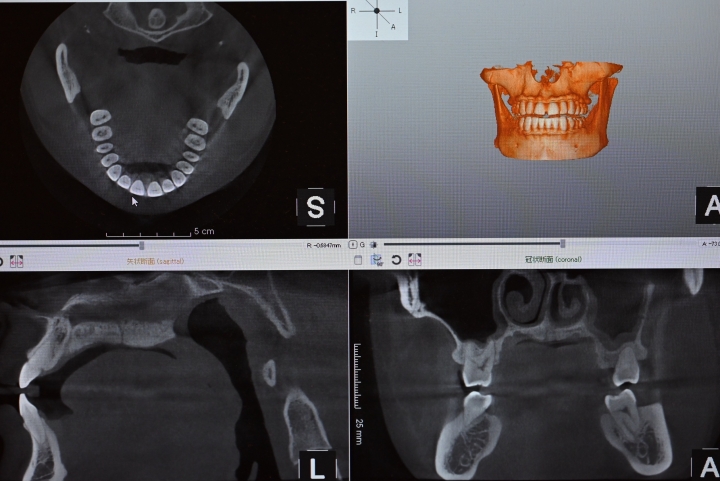

歯科用CTは、お口の中やあごの骨を 立体的(3D)に見ることができる特別なレントゲン です。

通常のレントゲンでは見えにくい部分も、詳しく確認できるので、より正確で安全な治療につながります。

• 神経や血管の位置

• 親知らずの生え方

• 歯ぐきや骨の状態